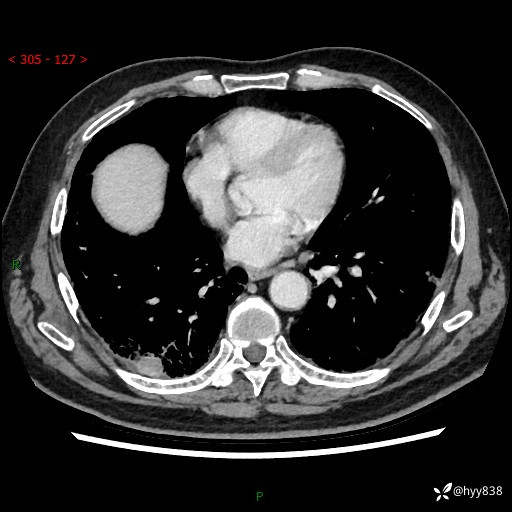

71岁/男,咳嗽伴气促半月。一年前肺手术史,又见两个结节,穿刺结果意外---结果公布~

【现病史】:患者半月前无明显诱因出现咳嗽、咳痰,为白色粘痰,无明显加重与缓解因素,伴气促,无发热,无大量脓痰,无胸痛、咯血,无哮鸣音,到我院就诊,胸部CT示右肺结节增大,并口服药物治疗无明显好转,具体用药不详,为求进一步治疗随来我院,经门诊以“孤立性肺结节”收入我科。 病程中患者精神、饮食可,睡眠不佳,大小便正常,体力下降,体重未见明显下降。

[既往史]:2022-06于当地第一人民医院确诊慢阻肺,现规律使用杰润(1次/日);2023-04-06于当地市第一人民医院行胸腔镜右肺上叶楔形切除术+右肺上叶切除术+淋巴结清扫术+胸膜黏连松解术,确诊为右肺鳞癌 pT2aN0M0 Ib期

【检查】:胸部CT平扫+增强